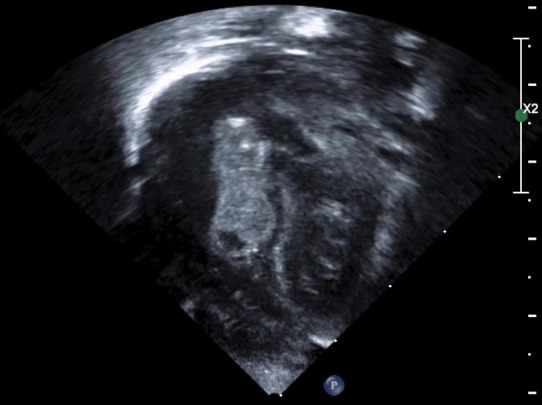

Infective atrial thrombus.